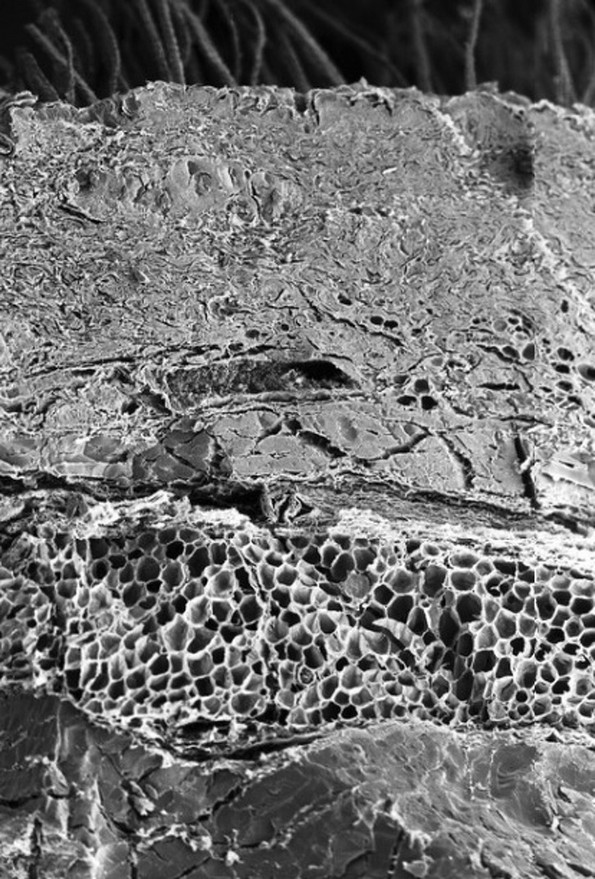

2. Коска